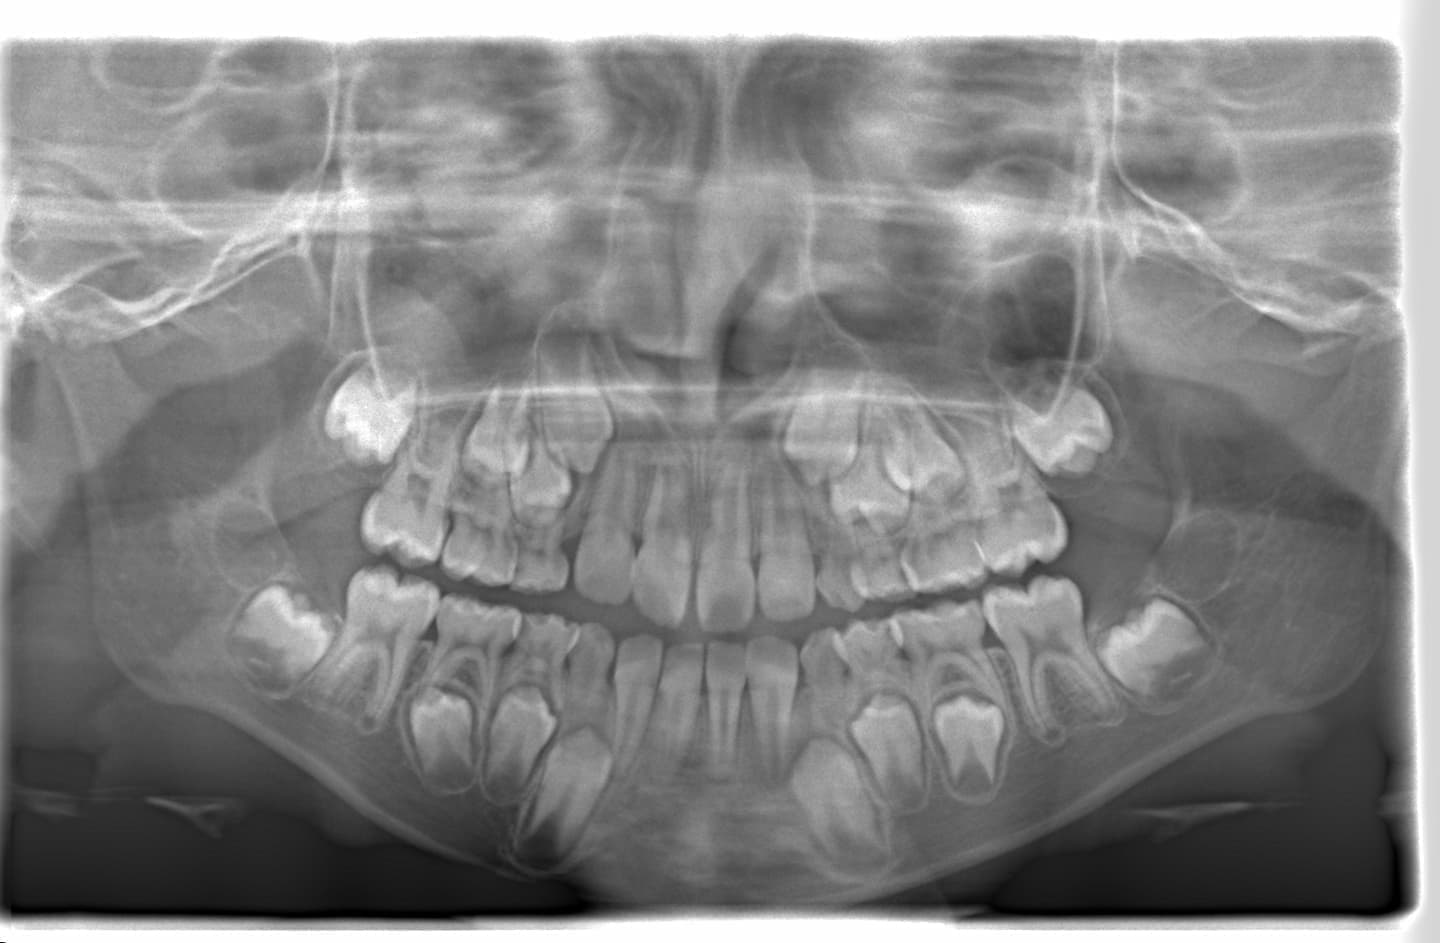

診断:初診時では右上3番の萌えるスペースがほとんどなく、顔と上顎と下顎の正中に対して、上顎前歯の正中が右にずれこんでいます。その影響で右上2番が右下乳歯Cと反対咬合になっています。放置すると、右上3番が埋伏歯になり、下顎の成長が左方向に流れるので、成長とともに顔面の非対称が増悪されることが予測されます。

分析診断:FXフェイシャルアキシスが83度で、咬合力が極端に弱い顔面骨格ではありません。上下顎の骨格的バランスも平均値内には収まっています。Upper Molar PTV値から、上顎の奥行きが少ないとわかります。前歯の位置、E-lineと下唇の位置等から、歯が大きくて顎が小さいディスクレパンシーケースであると診断されます。

分析診断:左右の骨格的非対称が少し認められます。上顔面の幅径はさほど狭くなありませんが、下顎や下顔面の幅径は狭いと出ています。

右上乳犬歯が既に脱落しており、右上犬歯の萌出スペースがゼロになっています。